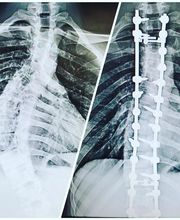

At Centers for Neurosurgery, Spine, and Orthopedics in Wayne, NJ, we ensure each patient understands their medical condition and treatment plan, and experiences quality human interactions at every step. We are a multi-specialty team of surgeons, pain control doctors, and physiatry doctors, who have developed a collective approach that optimizes each patient's treatment course, ultimately reducing the number of appointments and recovery time. CNSO offers services ranging from complex spine surgery, brain surgery, pain management, physical medicine, and rehabilitation so you can return to your daily activities quickly. Make an appointment with CNSO today at 1680 NJ-23, Ste. 250 in Wayne, NJ, 07470.